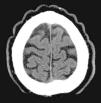

Detailed dermatologic and systemic medical history and physical examination, including endocrine and neurologic evaluation, detected none of the abnormalities associated with the primary nonessential forms. Scalp biopsy revealed a mild nonspecific superficial periadnexal and perivascular mononuclear inflammatory infiltrate in both patients. The following studies were performed to exclude causes of secondary CVG: plain x-rays of both hands, cerebral computed tomography (CT), routine blood tests with thyroid function, lipid profile, insulin-like growth factor1, antinuclear antibodies, and syphilis serology. The cerebral CT of patient 1 showed the skin folds affecting the scalp (Fig. 2). Other studies were normal or negative. Studies of the nail alterations (culture and histopathology) were only positive in patient 2 (growth of Trichophyton interdigitale), and treatment was prescribed with oral terbinafine (250mg/24h for 3 months). Genetic analysis was not performed in either patient.